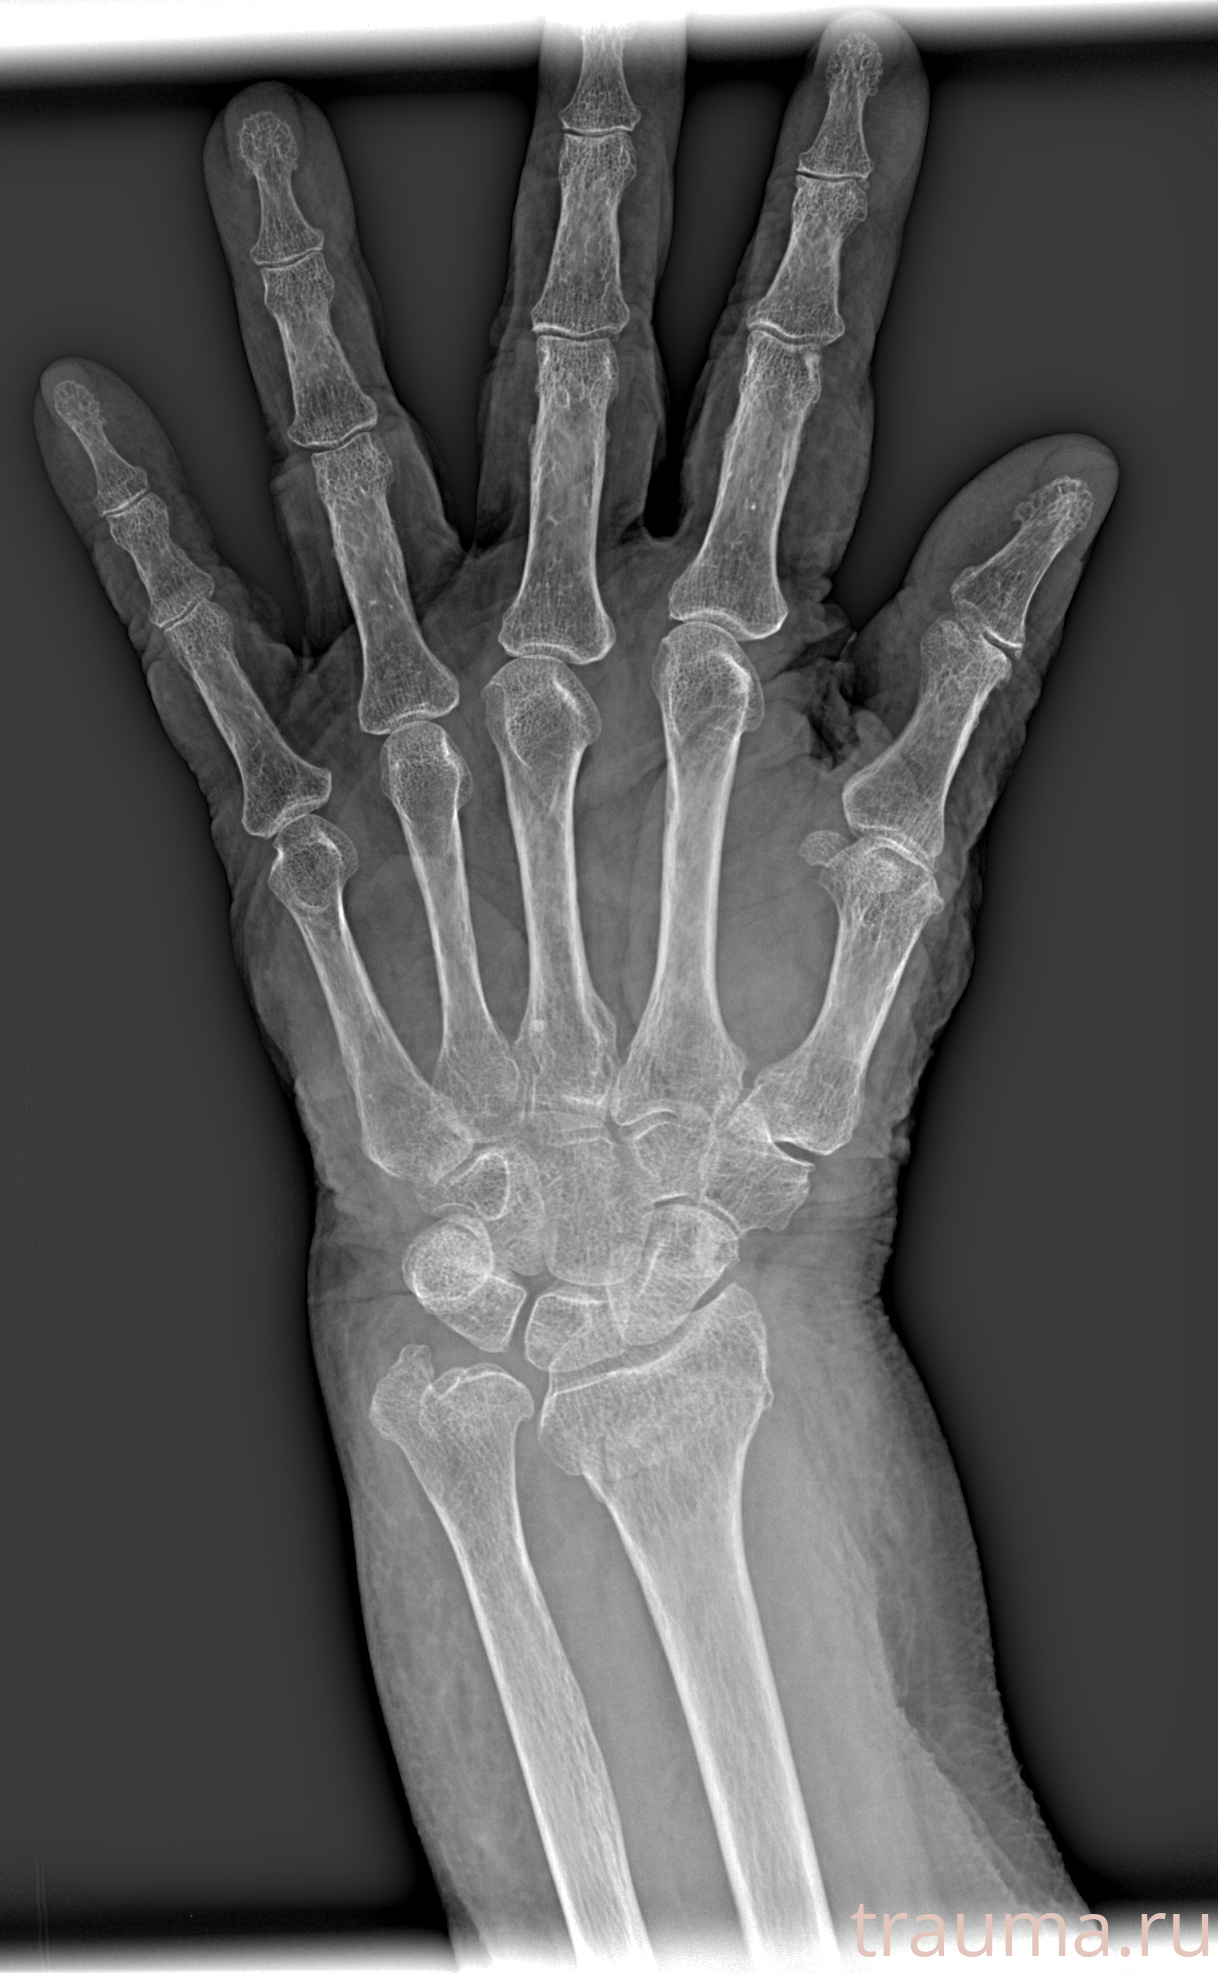

Рентгенограммы

Рентген на дому: по вашему адресу приезжает врач-рентгенолог, травматолог-ортопед с мобильным рентгеновским аппаратом, проводит диагностику травмы или заболевания, делает необходимые рентгенограммы, дает рекомендации по дальнейшему лечению. Получить качественные снимки в домашних условиях возможно благодаря уникальной методике, разработанной МосРентген Центром для института  Склифосовского